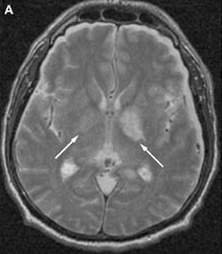

Tổn thương viêm màng não do phế cầu.